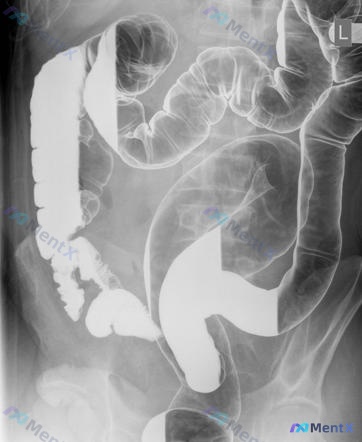

- 结肠钡灌肠X光:结肠充盈好,袋形规整,未见明显苹果核征、鹅卵石征或铅管征,黏膜皱襞规则